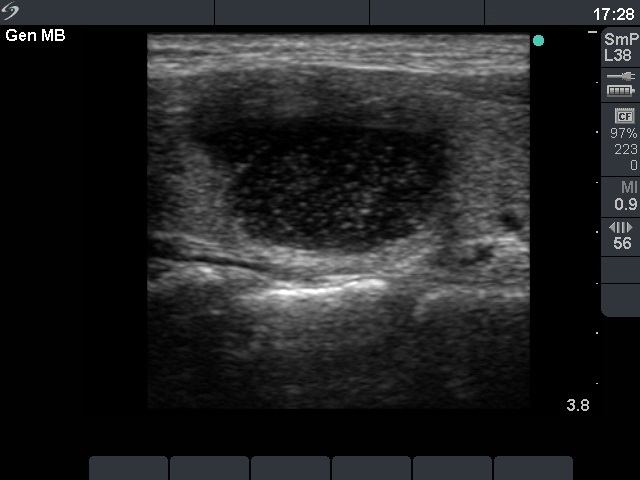

Benign nodular hyperplasia - Case 30. |

Clinical presentation: a 19-year-old woman with a newly discovered nodule.

Palpation: a firm nodule in the right lobe.

Functional state: euthyroidism with TSH-level 0.88 mIU/L.

Ultrasonography: a solitary cystic nodule in the right lobe with increased "blood flow".

Six mL brown cystic fluid was aspirated. Cytological report: benign, cystic degeneration.

Suggestion: regular follow-up examinations.